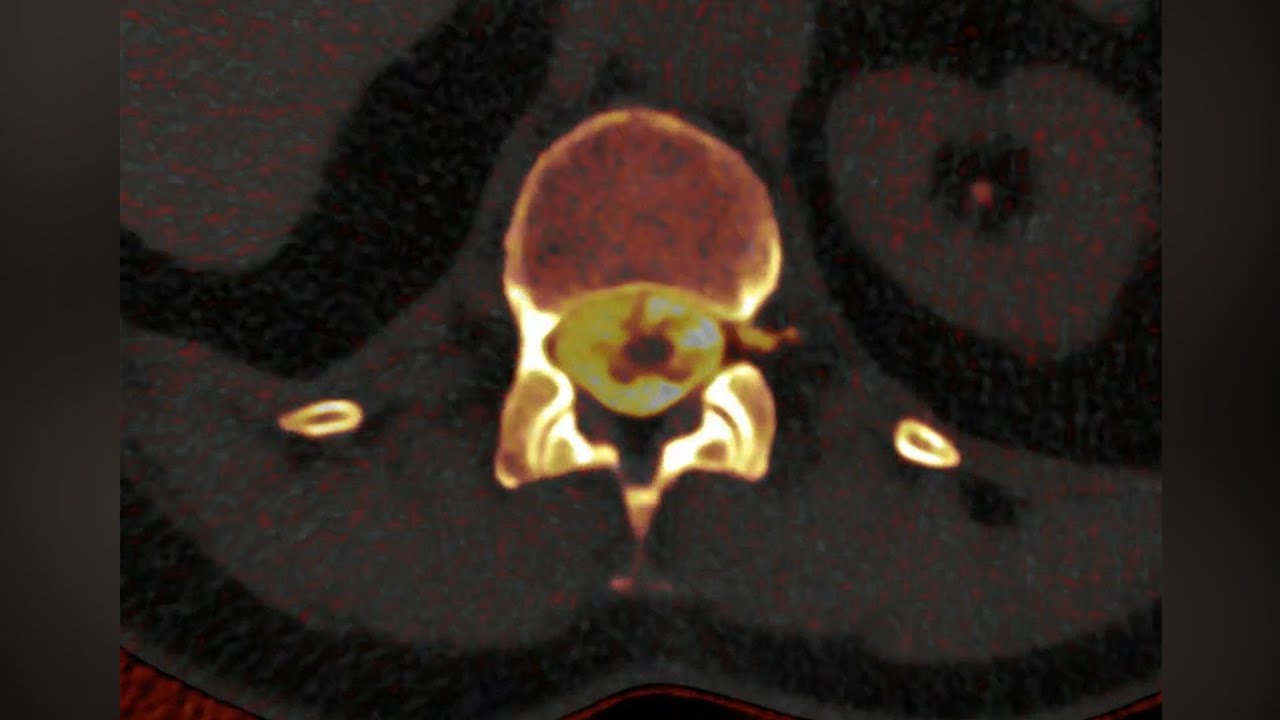

A new type of imaging technology is the photon counting CT (PCCT). For this kind of imaging, the machine emits a beam of X-ray photons, while special photon-counting detectors capture X-ray photons and measure their energy levels as they pass through a person’s body. The machine then uses that information to create an image, similar to a traditional CT scanner, but in this case with much higher resolution. In fact, PCCT images are often so much more finely detailed than other types of imaging, they can reveal things that other types of imaging technology miss.